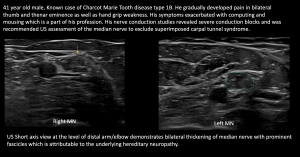

Fig 9: COMPRESSION UNDER FDS ARCH - Charcot Marie Tooth Disease with superimposed Bilateral Double Crush Syndrome: Compression at Pronator Tunnel and Carpal Tunnel

Fig 10: CHARCOT MARIE TOOTH DISEASE WITH SUPERIMPOSED COMPRESSION AT TWO SITES (DOUBLE CRUSH SYNDROME) Nerve thickening due to underlying hereditary neuropathy

Fig 11: CHARCOT MARIE TOOTH DISEASE WITH SUPERIMPOSED COMPRESSION AT TWO SITES (DOUBLE CRUSH SYNDROME) Compression of Right Median Nerve at the Pronator Tunnel

Fig 12: CHARCOT MARIE TOOTH DISEASE WITH SUPERIMPOSED COMPRESSION AT TWO SITES (B/L DOUBLE CRUSH SYNDROME) Compression of Right Median Nerve at the Carpal Tunnel

Fig 13: CHARCOT MARIE TOOTH DISEASE WITH SUPERIMPOSED COMPRESSION AT TWO SITES (DOUBLE CRUSH SYNDROME) Compression of Left Median Nerve at the Pronator and Carpal Tunnel